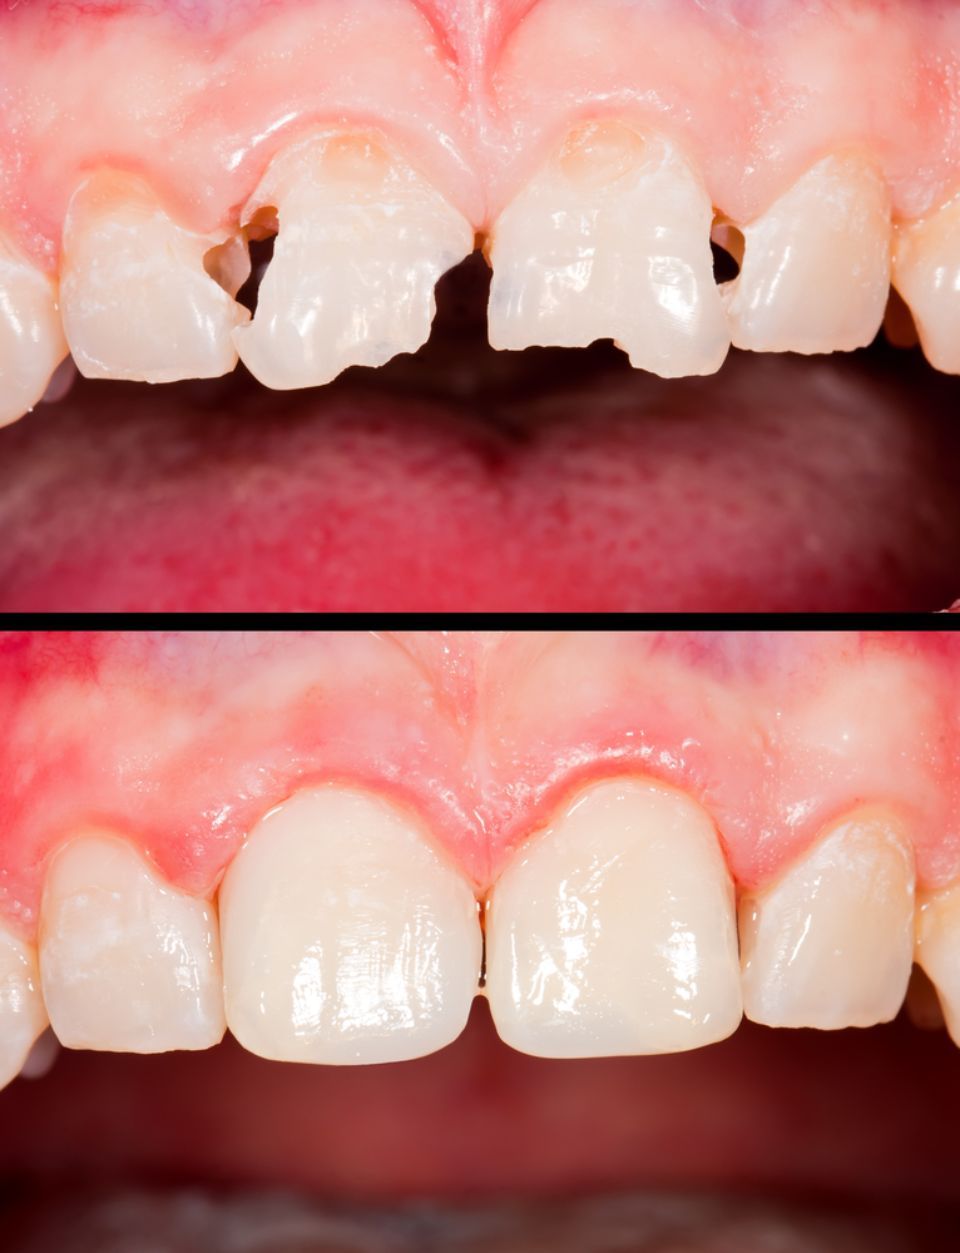

Restorative / Conservative Dentistry

As its name suggests, it tries to preserve by rebuilding teeth that have decayed or fractured, that have suffered trauma or are eroded; to preserve its function as a tooth.

Dental Aesthetics

The appearance of the teeth can be improved. The specialist team will evaluate each case to adopt the most appropriate technique: tooth whitening, composite restorations, ceramic veneers, metal-ceramic crowns, zirconium crowns, orthodontics, periodontal cosmetic surgery ...